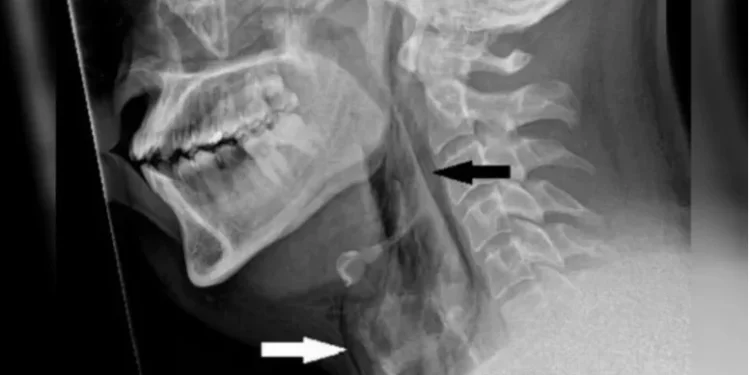

Após isso, o homem sentiu fortes dores no peito sendo obrigado a ir a um hospital em busca de atendimento de emergência. Um exame de imagem identificou a ruptura na traqueia de aproximadamente quatro milímetros.

“É raro, mas o acúmulo rápido de pressão na traqueia ao espirrar com o nariz apertado e a boca fechada ocasionou um rasgo traqueal, conforme os exames realizados no hospital de Dundee mostram”, destaca o texto da equipe médica.

Após cinco semanas, ele realizou uma nova tomografia computadorizada, que apontou a cicatrização completa do rasgo provocado pelo espirro interrompido. O paciente não apresentou sequelas, mas foi alertado dos riscos de repetir a ação.